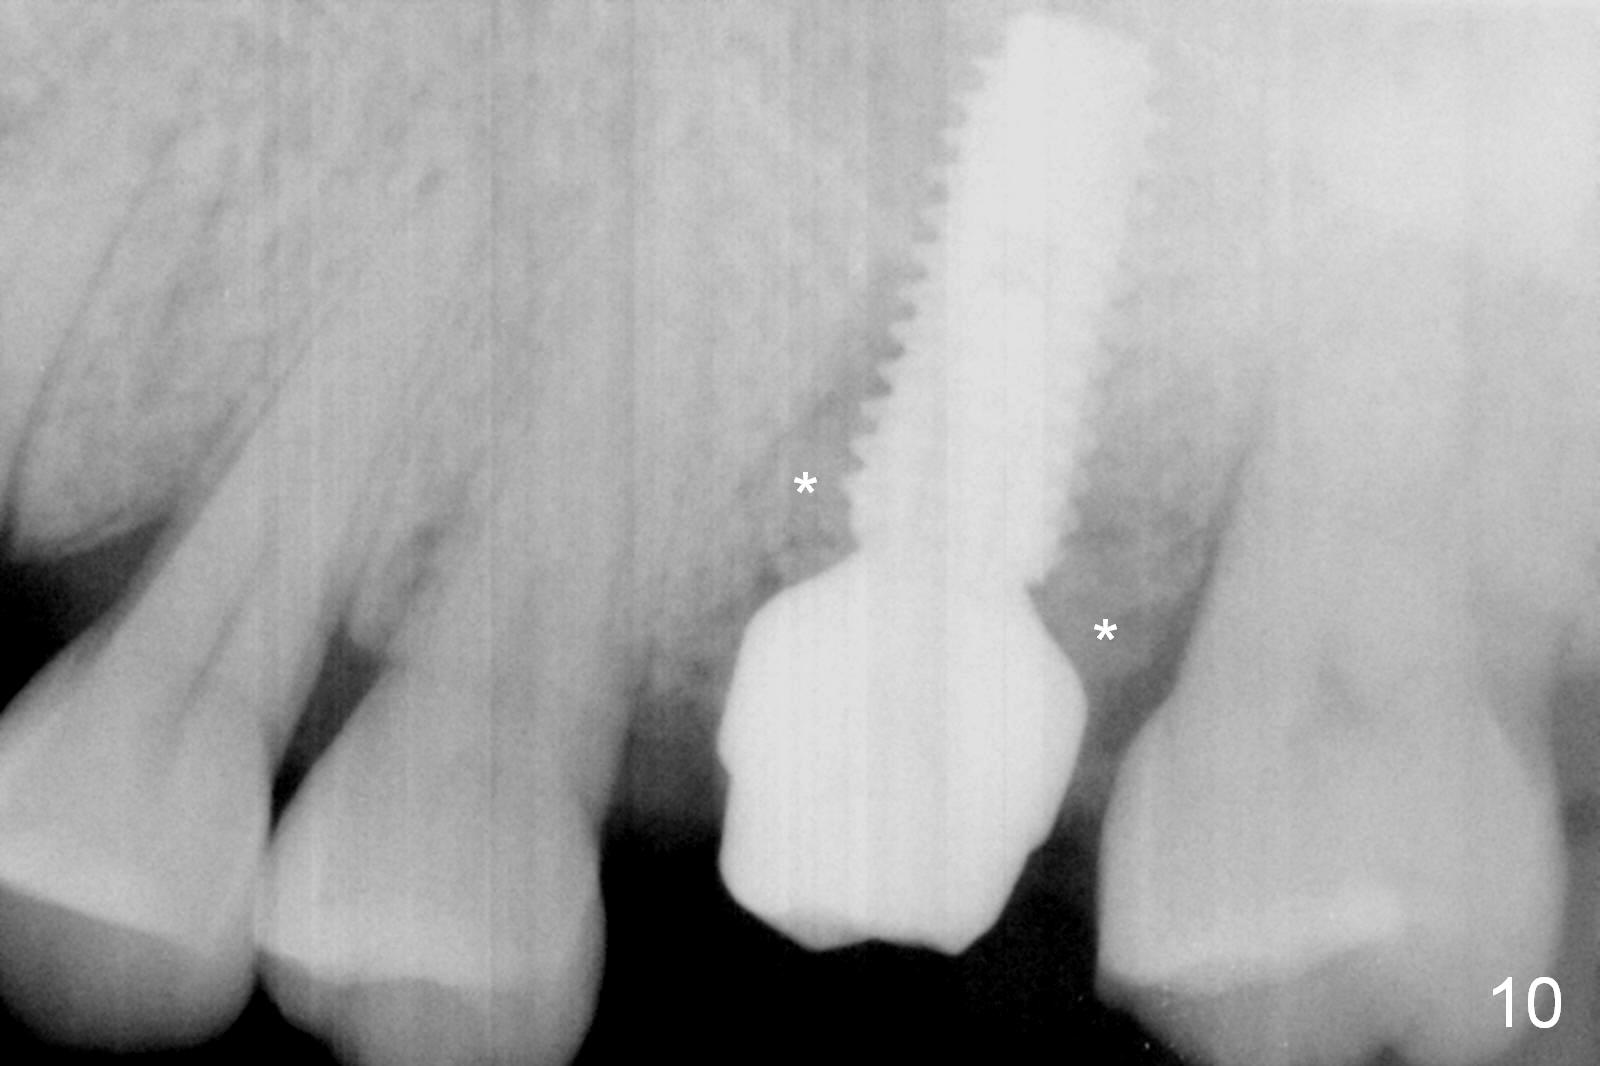

Osteotomy is initiated in the palatal slope of the septum 8 mm deep (Fig.8,9). A 5x11.5 mm implant is placed with insertion torque of 35 Ncm with ~ 2 mm sticking into the sinus with bone graft and 1.5-2.5 mm outside the septum. The latter is covered by bone graft (Fig.10 *). There is no nasal hemorrhage postop.